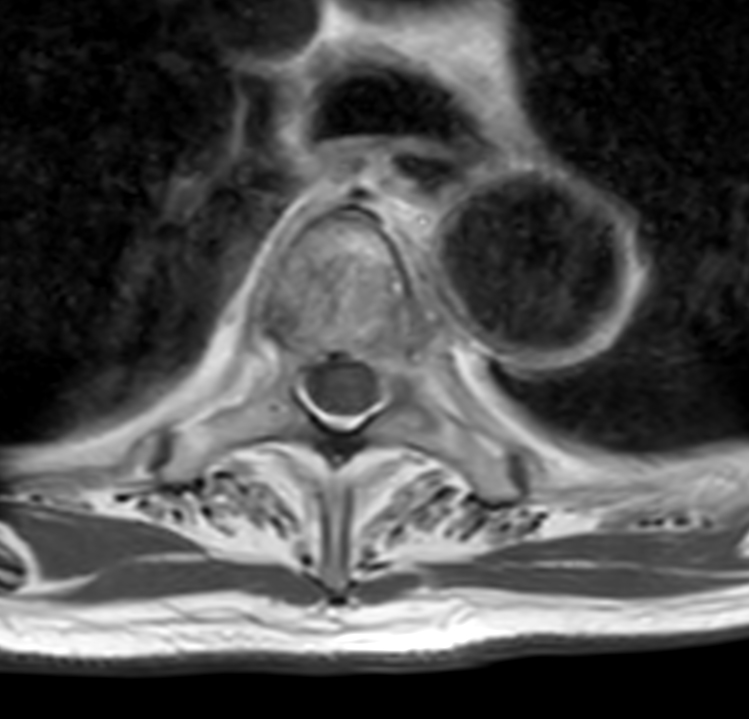

Axial T2w TSE (T4)

Axial T2w TSE - High res (T4)